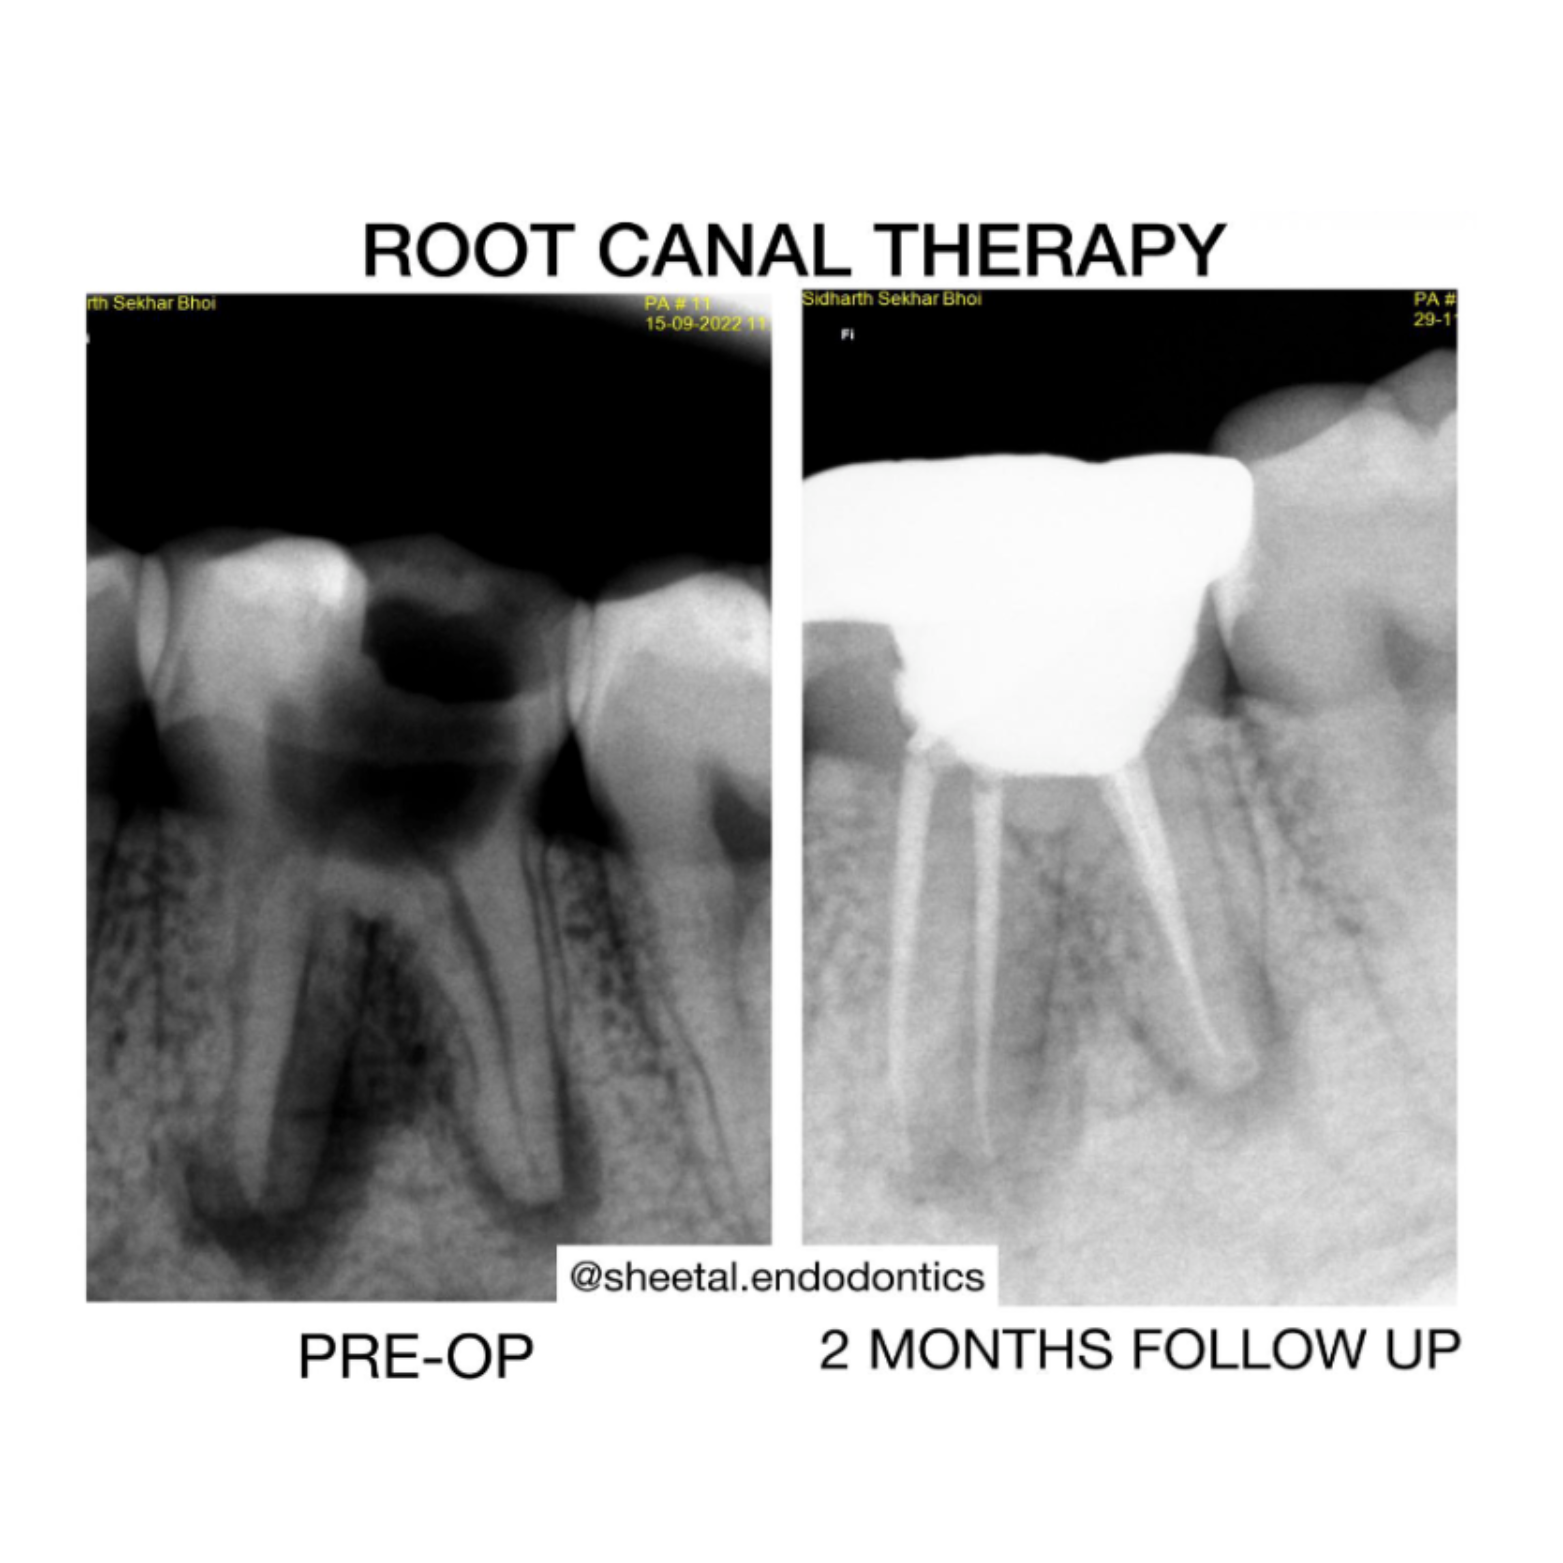

Root Canal Treatment

Root canal treatments are performed under complete saliva isolation with rubber dams and high magnification.